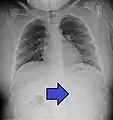

A coin seen on AP CXR in the esophagus